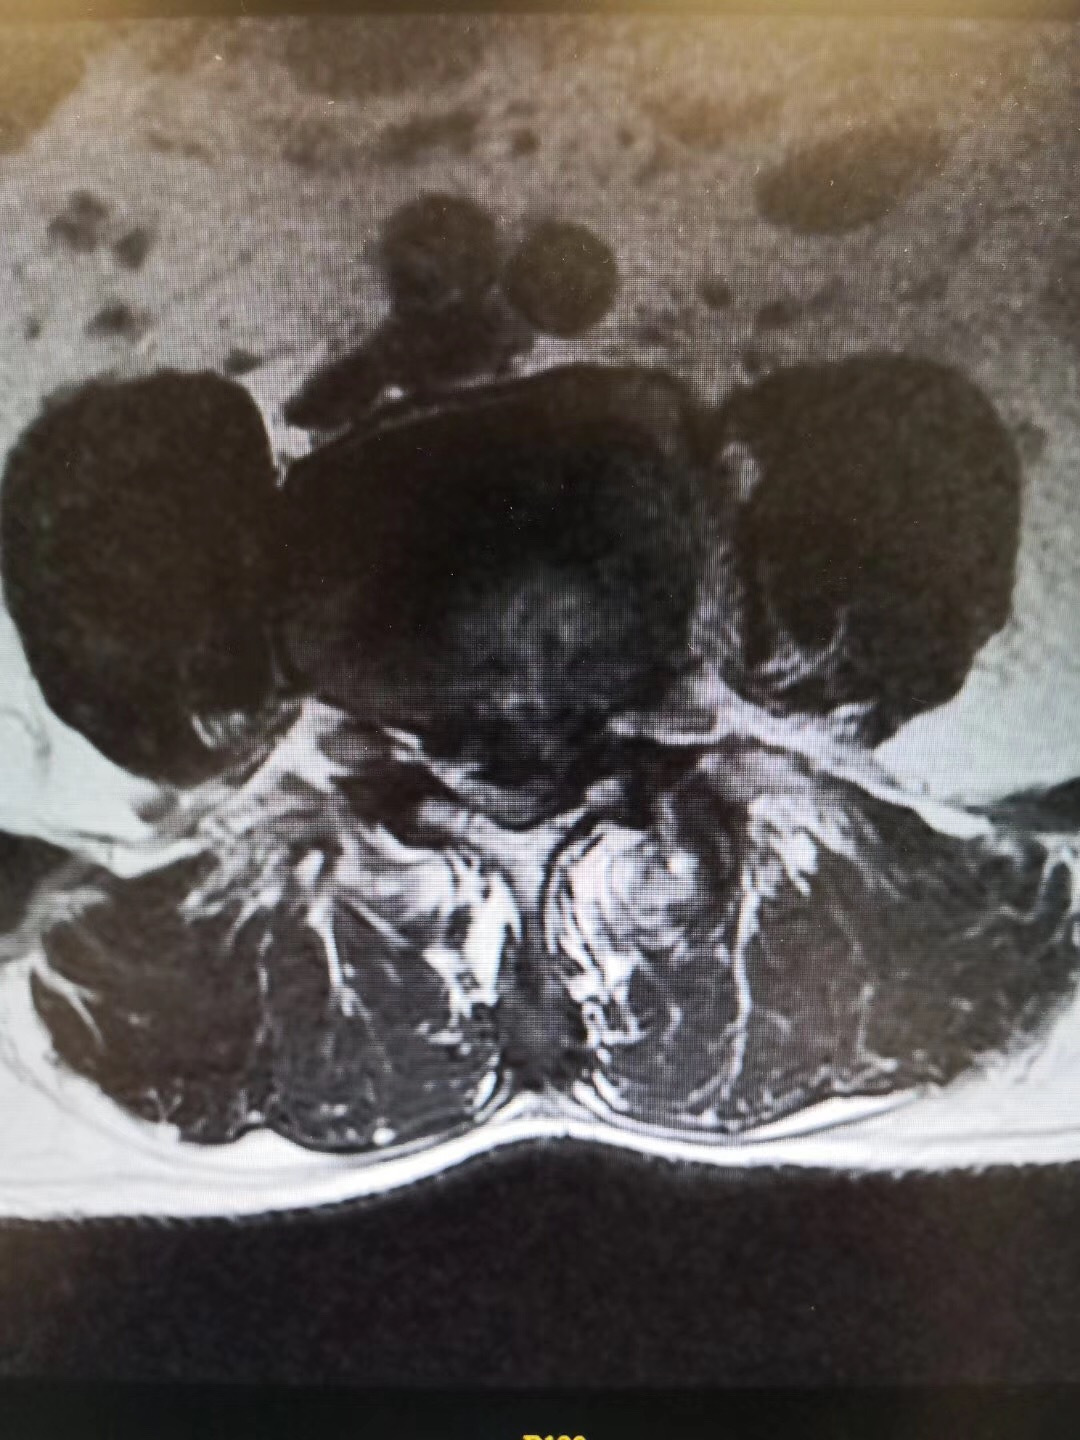

症状:双下肢麻痛伴间歇性跛行1年,行走100米即出现双下肢麻痛,严重影响生活。

诊断:腰椎间盘突出伴椎管狭窄症(L4/5节段),腰椎不稳定(L4/5节段),予施行“后路腰椎管减压固定融合术”治疗。